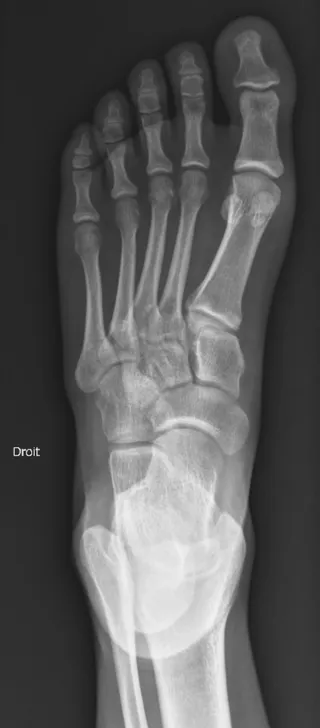

- Permet de rechercher une fracture.

- Permet de rechercher une arthrose ou une arthrite.

- Permet de rechercher des calcifications des tissus mous.

- Permet de visualiser la plupart des tumeurs osseuses bénignes ou malignes.